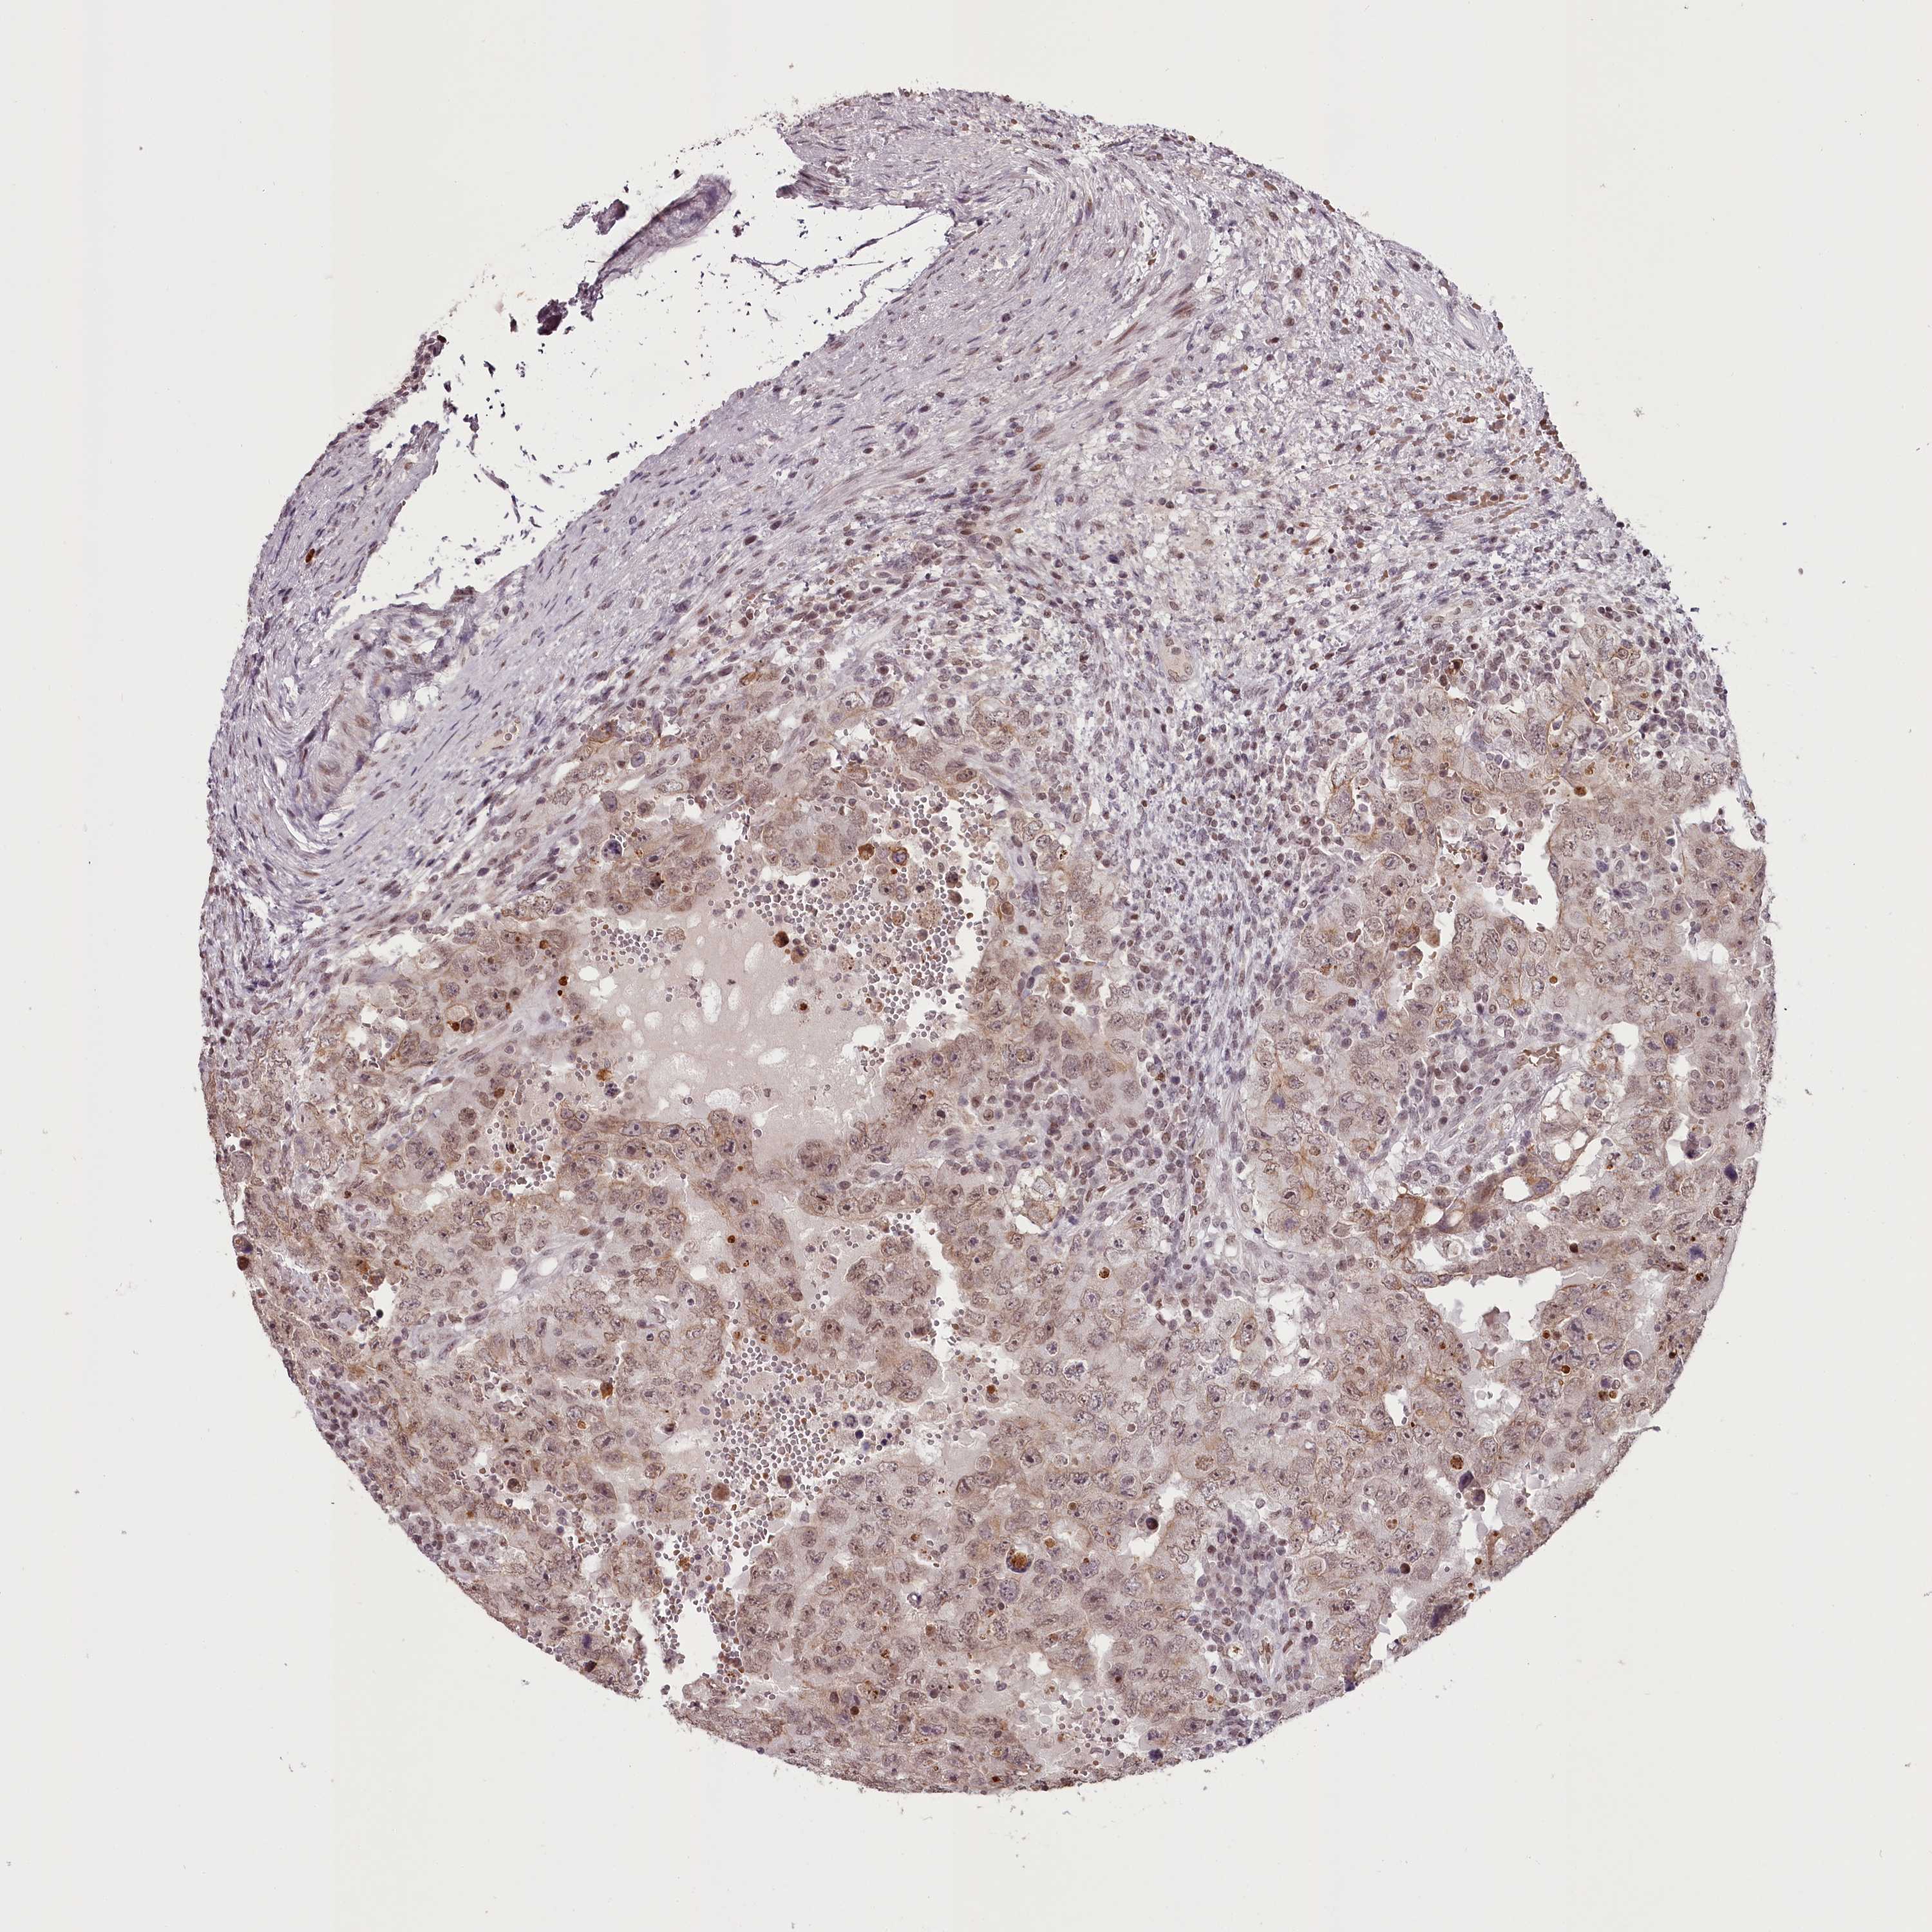

TESTIS CANCER - Protein expressioni

A mouse-over function shows sample information and annotation data. Click on an image to view it in a full screen mode. Samples can be filtered based on level of antibody staining by selecting one or several of the following categories: high, medium, low and not detected. The assay and annotation is described here.

Note that samples used for immunohistochemistry by the Human Protein Atlas do not correspond to samples in the TCGA dataset.

Antibody stainingi

Antibody staining in the annotated cell types in the current human tissue is reported as not detected, low, medium, or high, based on conventional immunohistochemistry profiling in selected tissues. This score is based on the combination of the staining intensity and fraction of stained cells.

Each image is clickable and will lead to virtual microscopy that enables deeper exploration of all samples and also displays staining intensity scores, fraction scores and subcellular localization as well as patient and tissue information for each sample.

Antibody HPA038732

Antibody HPA038733

Carcinoma, Embryonal, NOS

Seminoma, NOS

Urothelial carcinoma, High grade